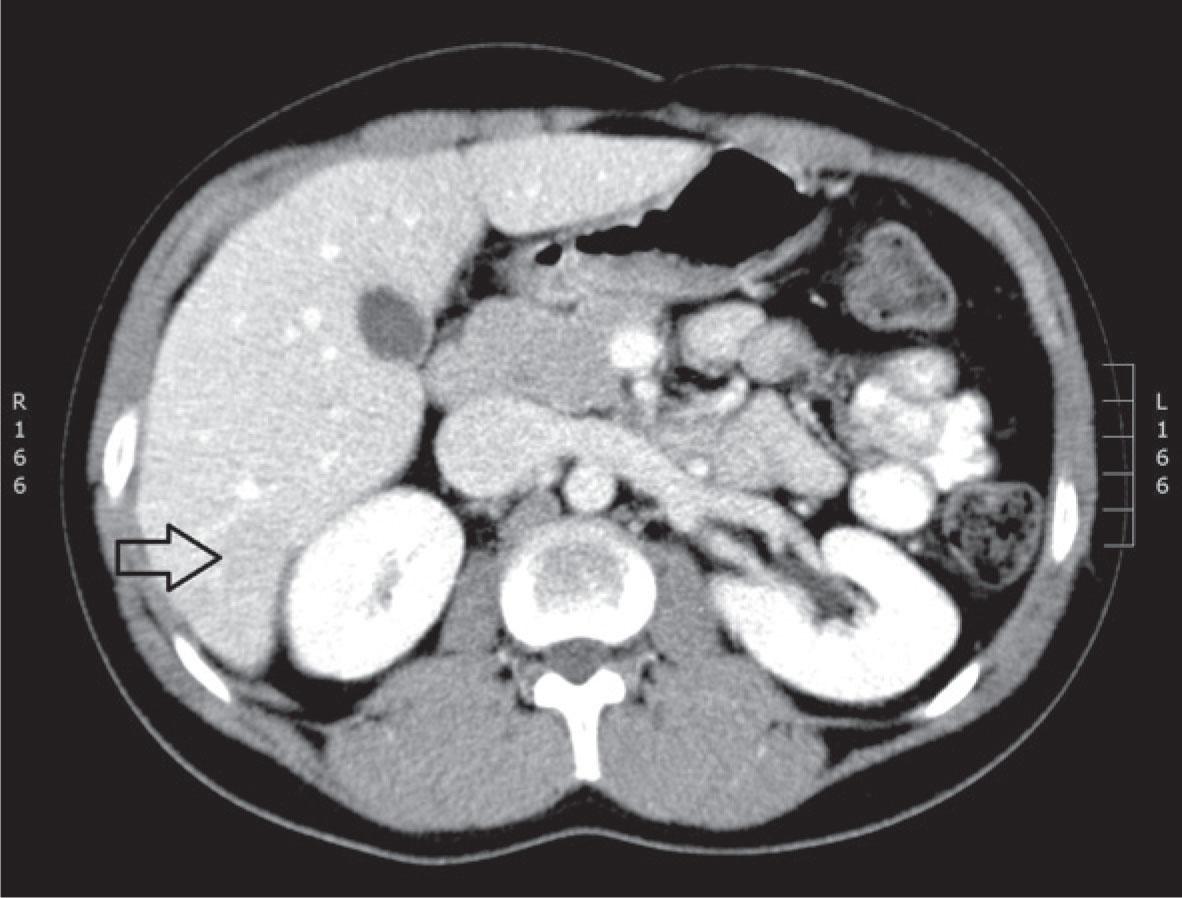

CT; portal phase of contrast enhancement - subtle hypodense lesions in 6th liver segment.